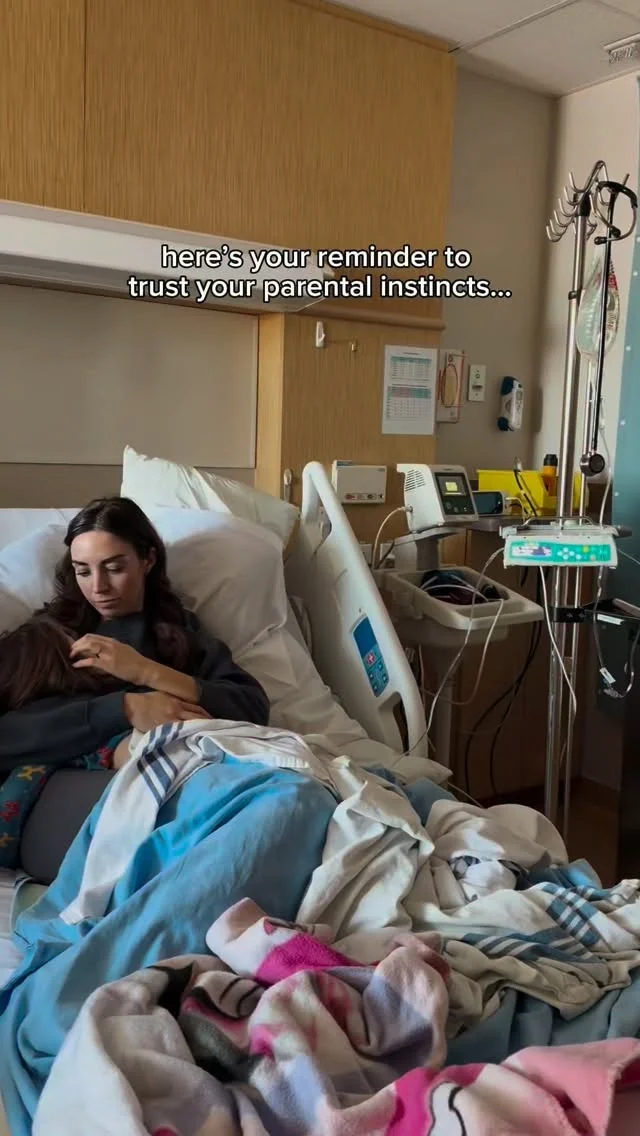

Nothing warms my heart like helping my family feel their best And obv...

Nothing warms my heart like helping my family feel their best And obviously that always starts with the foundations first: eating enough, hydrating, managing stress, sleeping, exercising (not yet for my sister lol), and...